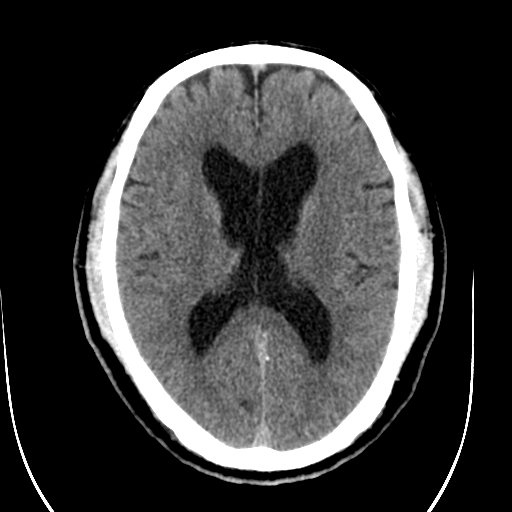

标题: CT28335:男,58岁,请各位看看是不是有脑积水,蝶窦内高密 [打印本页]

标题: CT28335:男,58岁,请各位看看是不是有脑积水,蝶窦内高密

轻度积水,蝶窦正常。

脑积水!建议行mri!

1)脑积水。2)副鼻窦炎。